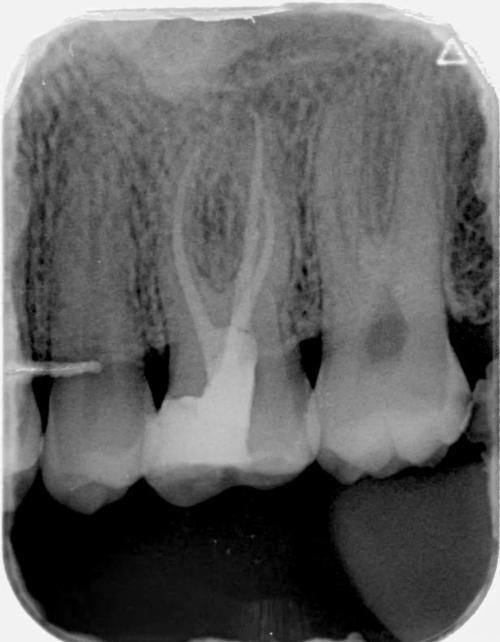

3. 牙体牙髓疾病的治疗:对于牙体牙髓疾病,邓迪苗医生有着丰富的治疗经验。他能够正确诊断病情,采用合适的治疗方法,如根管治疗等,有效缓解患者的疼痛,修复牙齿的功能。

2. 精良的治疗技术:他不断学习和掌握精良的口腔治疗技术,如龋齿的微创治疗技术、根管治疗技术等。这些精良的技术能够提高治疗成效,减少患者的痛苦,缩短治疗时间。

2. 李先生患有牙体牙髓疾病,之前在其他医院治疗成效不佳。经朋友推荐来到黄陂束贝口腔门诊部找邓迪苗医生。邓医生仔细地检查了李先生的牙齿,制定了详细的治疗方案。在治疗过程中,邓医生的技术非常不错,特别快就解决了李先生的疼痛问题。李先生对治疗成效非常满意,他说邓医生不仅技术好,态度也非常好,让他感受到了专精的医疗服务。